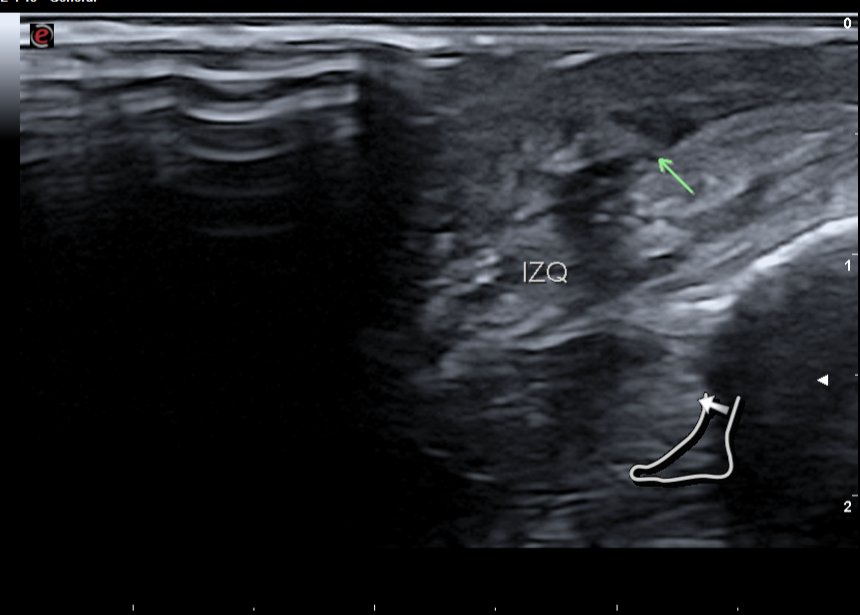

Solicito ecografía reglada tras no mejoría en 1 mes, con curas y cambios en tratamiento antibiótico, donde se aprecia cambios postquirúrgicos sin datos de colecciones y se aprecia posible remanente milimétrico de cuerpo extraño. Nueva derivación a cirugía general para valoración de reintervención.